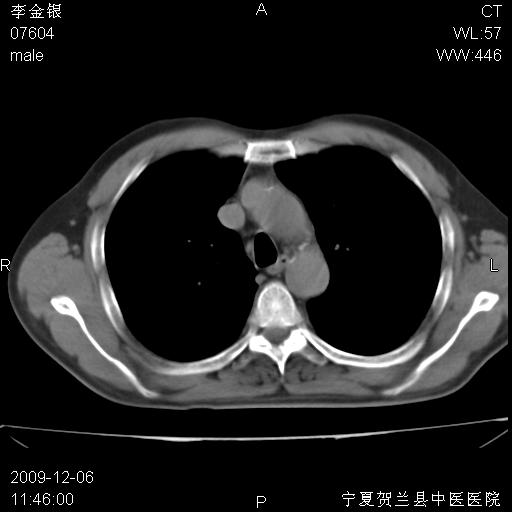

该病人 ,男,62岁,主因咳痰带血两天

右肺上叶后段支气管阻塞,右上肺门占位,相应肺段阻塞性肺炎,右肺门有淋巴结肿大。诊断右肺上叶中心型肺癌,阻塞性肺肺炎、右肺门淋巴结转移。

考虑右侧中央型肺癌并阻塞性炎症及不张,建议ct增强!!

右上叶支气管狭窄,管壁增厚,远端斑片状软组织影,病灶邻近叶间裂,叶间裂无移位。

诊断右肺中央型肺癌。

那个片影应该大部分都是病灶,病灶沿肺段支气管分支生长,后段完全显示不清、闭塞。若为不张应该伴有叶裂的移位,若为炎症应有空气支气管征。

考虑右侧中央型肺癌伴右肺上叶后段阻塞性炎症、肺不张、右肺门和纵隔淋巴结肿大。